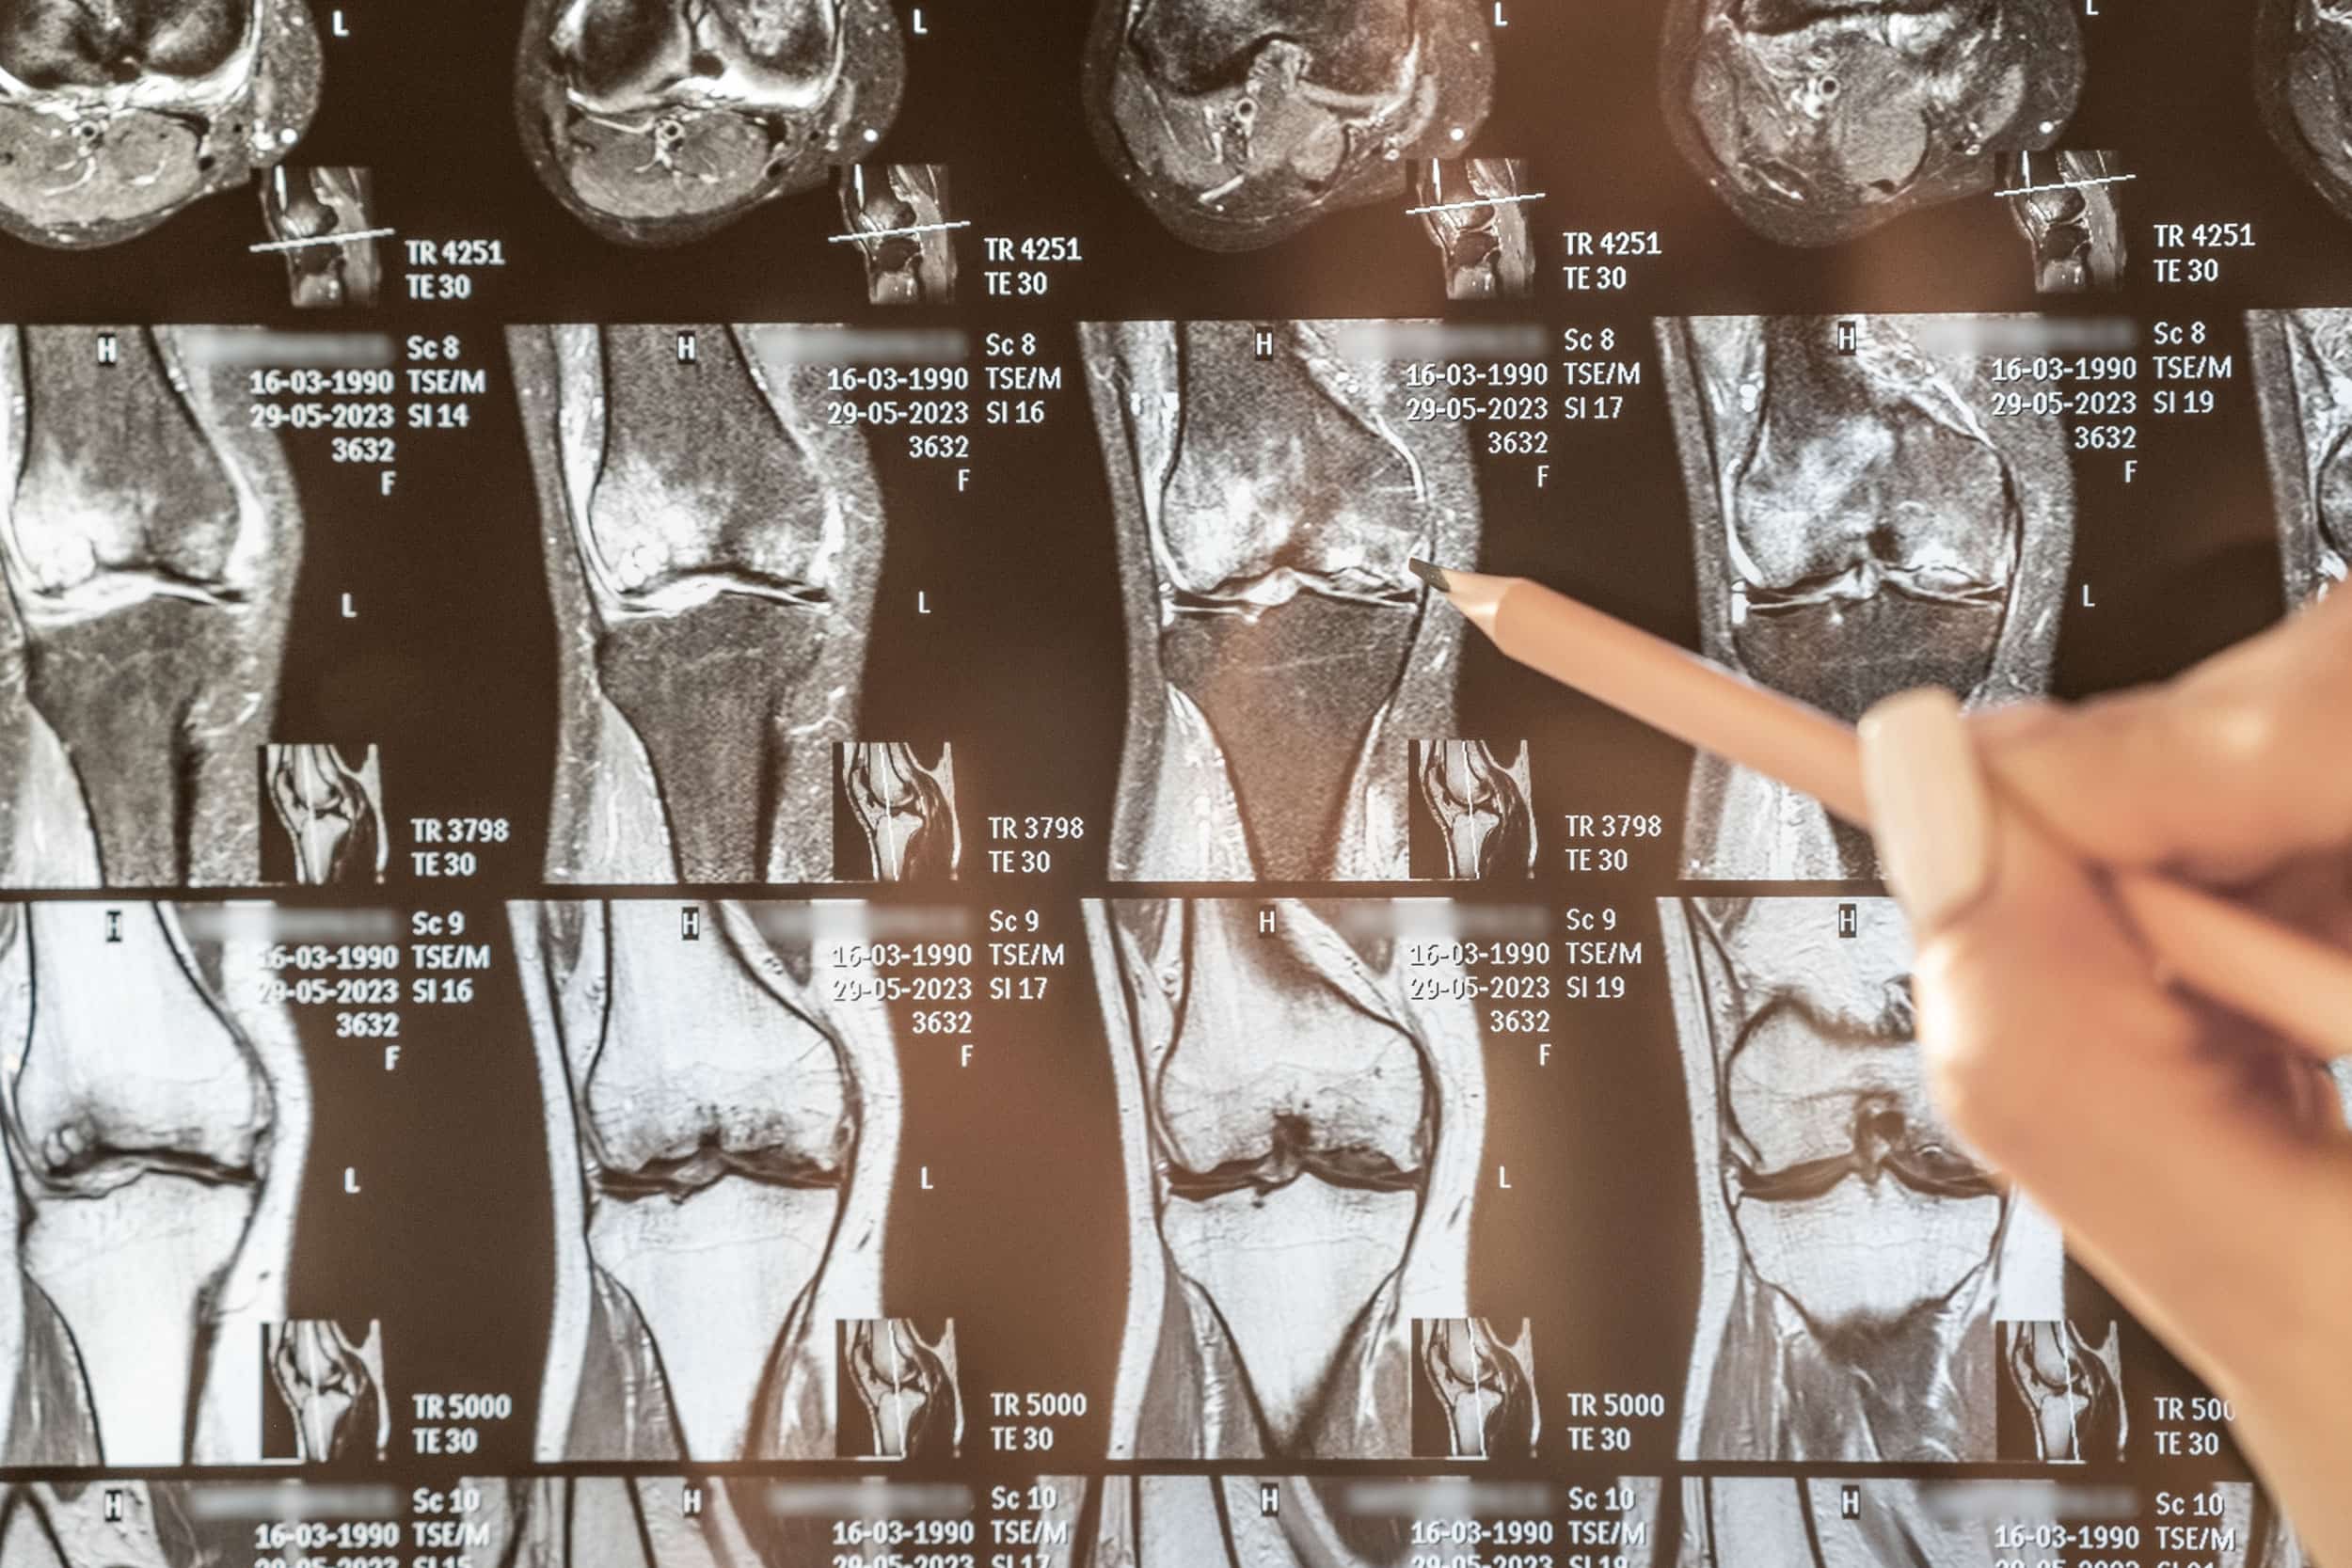

Monter les escaliers devient difficile, la marche plus lourde, et les activités sportives que vous aimiez se transforment en épreuve. L’arthrose du genou, aussi appelée gonarthrose, est une pathologie fréquente qui touche de nombreuses personnes, sportifs ou non. Elle résulte d’une usure progressive du cartilage et provoque douleurs, raideurs et parfois gonflements.

L’arthrose du genou se développe suite à une usure progressive du cartilage qui recouvre les surfaces articulaires. Plusieurs facteurs contribuent à cette dégradation :

L’arthrose n’est pas une fatalité liée uniquement à l’âge. Elle est souvent le résultat d’un ensemble de facteurs mécaniques et biologiques.